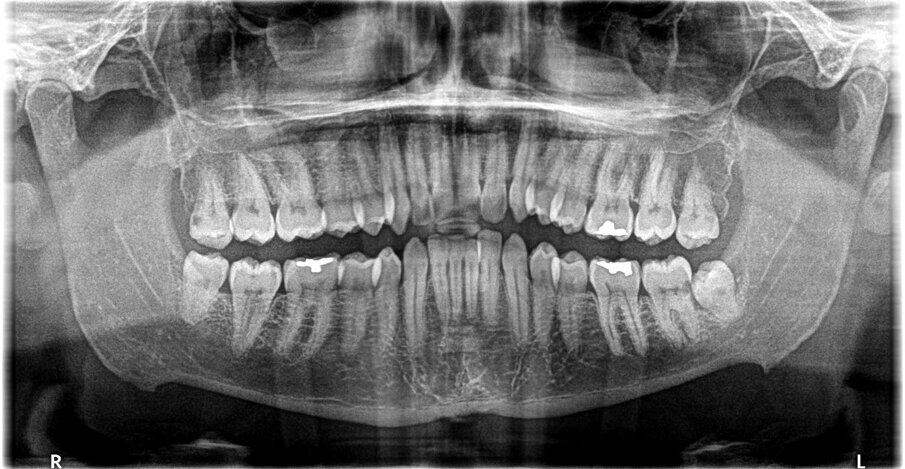

A questo proposito si presenta il caso della paziente F.C., 48 anni, che presentava un 3.8 in seminclusione. A livello anamnestico la paziente riferiva a carico del suddetto elemento, reiterati episodi flogistici e algici. A livello radiografico veniva inoltre riscontrata la presenza di una importante lesione cariosa sulla superficie distale del contiguo 3.7 (Fig. 1). Si è pertanto deciso di procedere alla estrazione chirurgica del 3.8 secondo tecnica convenzionale con incisione e scollamento del lembo muco-periosteo, ostectomia vestibolo-mesiale, avulsione dell’elemento dentario curetage dell’alveolo residuo e sutura a mezzo di punti staccati. L’intera seduta si è svolta senza complicazioni e ha avuto la durata complessiva di 25 minuti. (Fig. 2)

Fig. 2 - Immagine rx di controllo postoperatoria.